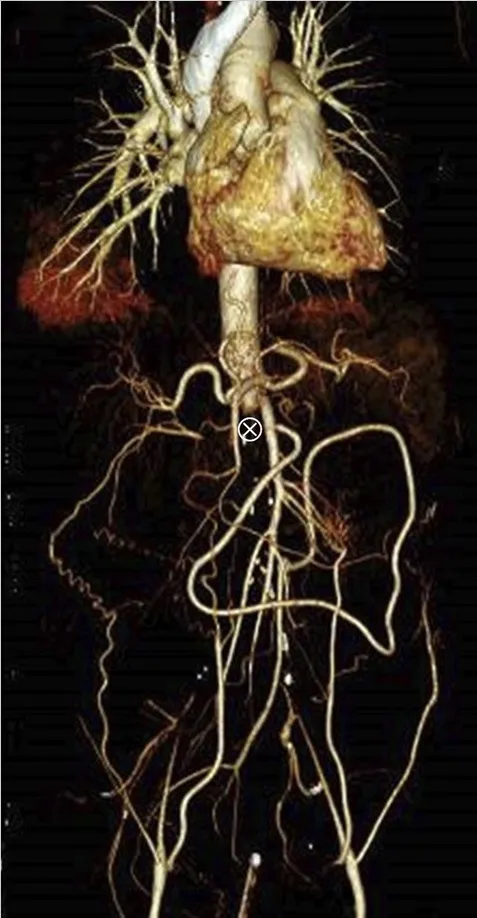

Se realizó una ecografía renal con Doppler que mostró ecogenicidad y tamaño renal normales, pero signos de oclusión aórtica en la emergencia de la arteria mesentérica superior, lo que fue confirmado por una tomografía computarizada con contraste (Figura 1).

La TC también reveló una importante circulación colateral en la pared abdominal, lo que permitía un suministro sanguíneo suficiente a las extremidades inferiores. Solo el riñón izquierdo mostró captación residual de contraste (Figura 1), lo que sugería un riñón derecho isquémico.

Se realizó una cirugía de emergencia con un bypass aortobifemoral y anastomosis de la arteria renal izquierda, asumiendo que el riñón izquierdo aún estaba viable. La paciente requirió hemodiálisis después de la cirugía.

TC con contraste (reconstrucción 3D) mostrando oclusión aguda de la aorta justo superior a la arteria mesentérica. (A) Oclusión aórtica justo superior a la arteria mesentérica (marcada con un ⊗) junto con vasos colaterales en la pared abdominal (B) Riñón izquierdo con realce de contraste y riñón derecho sin realce, lo que sugiere falta de perfusión renal.